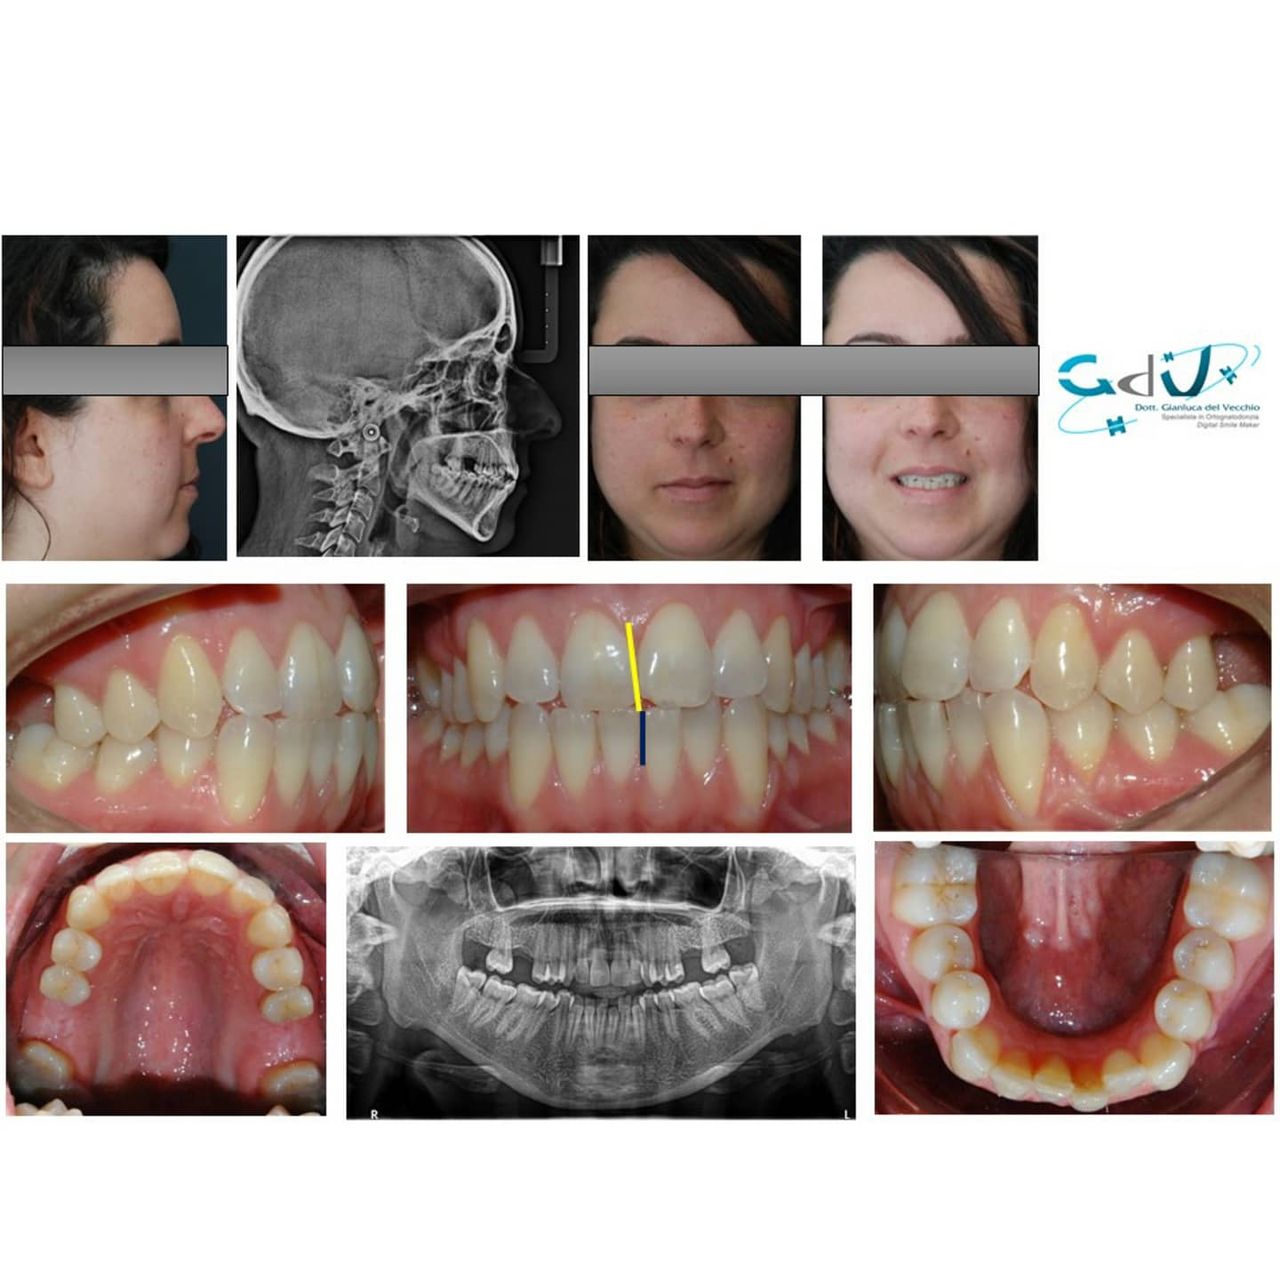

Il dottor Gianluca del Vecchio si occupa esclusivamente di ortognatodonzia, grazie anche alla collaborazione multidisciplinare di una équipe davvero entusiasmante e all’utilizzo di strumenti diagnostici e terapeutici all’avanguardia in ortognatodonzia. Particolare è la sua capacità di condurre i giovani pazienti ad affrontare, nella massima sicurezza emotiva e clinica, qualsiasi eventuale condizione di dolore derivante, ad esempio, da carie o da altre patologie, ma soprattutto di risolvere tutte quelle condizioni di “denti storti”, così spesso causa di disagio psicologico o di fenomeni deprecabili, quale il bullismo.

Il suo percorso formativo, iniziato con laurea in odontoiatria con il massimo dei voti, è proseguito col costante obiettivo di raggiungere una eccellenza clinica, attraverso la specifica specializzazione, arricchita in seguito da diversi master in Europa e uno anche in America a Tucson, famoso centro ortodontico a livello mondiale.

Queste le ragioni che consentono di trattare le malocclusioni, sia dei bambini che degli adulti, con protocolli scientificamente validati come i più veloci, affidabili e confortevoli.